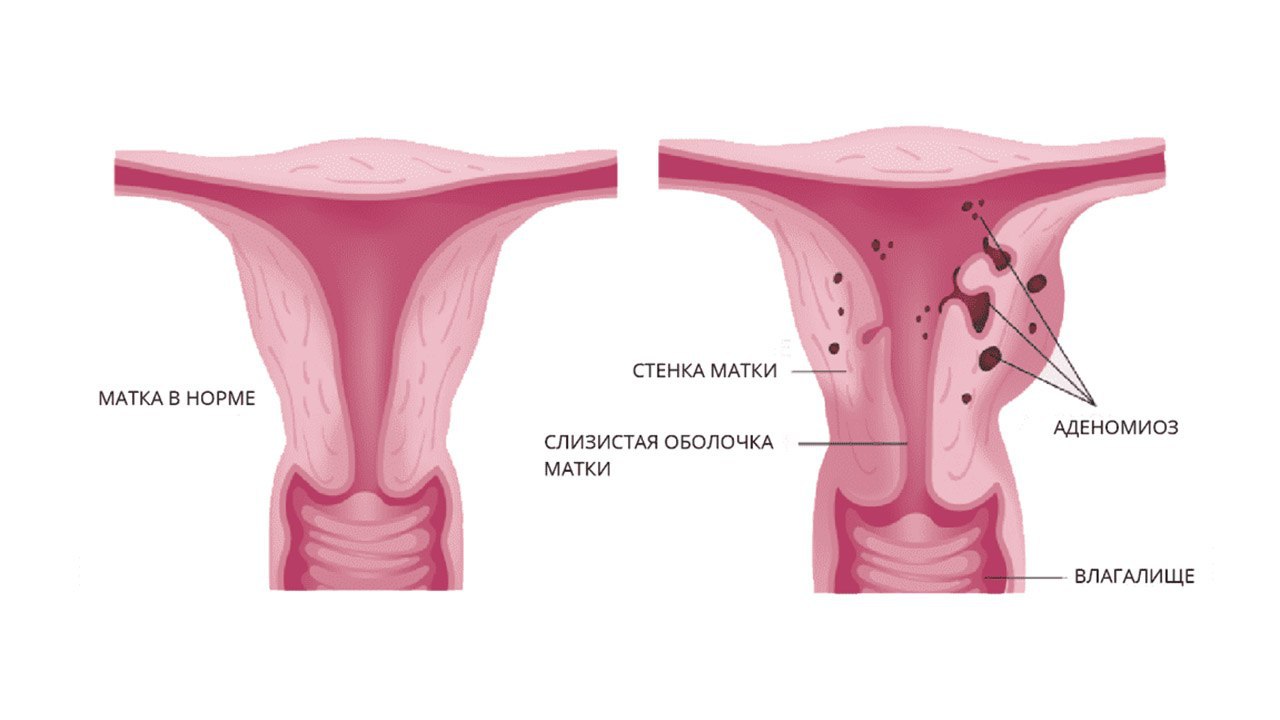

Аденомиоз – это состояние, когда эндометрий (внутренняя оболочка матки) проникает в её мышечный слой. Это одна из форм эндометриоза. Симптомы включают продолжительные и обильные месячные, кровянистые и коричневые выделения между циклами, высокую интенсивность предменструального синдрома, болезненные месячные и дискомфорт при половом контакте. Такое заболевание чаще всего встречается у женщин в репродуктивном возрасте и сходит на нет после менопаузы. Для установления диагноза используются гинекологический осмотр, а также инструментальные и лабораторные методы исследования. Варианты лечения могут быть медикаментозными, хирургическими или комбинированными.

Аденомиоз характеризуется внедрением эндометрия в подлежащие слои матки. В основном, это заболевание затрагивает женщин в репродуктивном возрасте, особенно после 27-30 лет. В редких случаях может быть врожденным. Заболевание часто проходит самостоятельно после менопаузы. Это третье по распространенности гинекологическое нарушение после аднексита и миомы. Аденомиоз часто сочетается с миомой матки. Современные гинекологи отмечают увеличение случаев аденомиоза, что может быть обусловлено увеличением числа иммунных нарушений и улучшением диагностических методов.

Аденомиоз представляет собой форму эндометриоза, когда клетки внутреннего слоя матки, эндометрия, начинают активно расти за ее пределами, например, в маточных трубах, яичниках или даже в системах пищеварения, дыхания и мочевыделения. Эти клетки могут мигрировать разными способами: контактно, через лимфу или кровь. Несмотря на их необычное месторасположение, эндометриоз не классифицируется как опухоль, так как эти "блуждающие" клетки сохраняют свою обычную структуру.